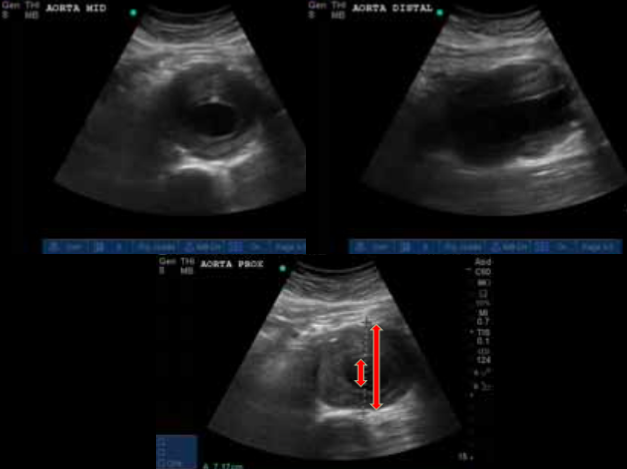

How should you measure the aorta when assessing for aortic aneurism?

Wall to wall, include plaques

What does this patient have going on with his aorta?

Aortic dissection